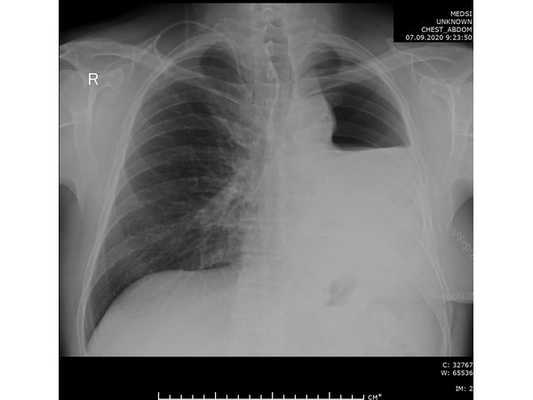

При дальнейшем дообследовании, по данным рентгенографии и компьютерной томографии органов грудной клетки выявлено новообразование в нижней доле левого лёгкого. После этого пациент был направлен на консультацию к торакальному онкологу.

Чтобы провести первичное стадирование опухоли, пациенту проведена позитронно-эмиссионная томография в сочетании с компьютерной томографией (ПЭТ-КТ). По данным исследования, выявлена метаболически активная опухоль в корне левого лёгкого с бугристыми контурами размерами 41 х 43 мм. В толще опухоли проходят нижнедолевой бронх и бронх 6-го сегмента левого лёгкого, просветы бронхов значительно сужены. Нижняя доля левого лёгкого уменьшена в размерах за счёт того, что сегменты 6, 9 и 10 субтотально (частично) инфильтрированы и безвоздушны. Лимфатические узлы корня лёгкого и средостения не увеличены в размерах и не накапливают радиофармпрепарат (РФП), который был введён пациенту перед обследованием внутривенно. Других очаговых образований и очагов гиперметаболизма в организме не обнаружено.

При этом отмечено, что опухоль распространяется в средостение по нижней стенке левого главного бронха и широко прилежит к нижнегрудному отделу аорты (по заключению специалиста ПЭТ-КТ — имеется инвазия опухоли в ткани средостения и возможное врастание в стенку аорты). При самостоятельном пересмотре изображений отмечено, что "опухолевая" ткань, которая распространяется по нижней стенке левого главного бронха в средостение, не накапливает РФП (т. е. не является злокачественной), а стенка аорты в области "инвазии" опухоли имеет ровный чёткий контур и адвентициальную границу, что также свидетельствует об отсутствии онкологического процесса в этой области.

Основное заболевание: Центральный немелкоклеточный рак нижней доли левого лёгкого, сT2bN0M0, IIА стадия. (T2b — опухоль более 5 см, но менее 7 см в наибольшем измерении; N0 — нет метастазов в региональных лимфатических узлах; M0 — нет отдалённых метастазов).

Проведена профилактическая стандартная антибактериальная терапия в течение пяти суток. По данным контрольной рентгенографии, отмечено смещение средостения в оперированную сторону.